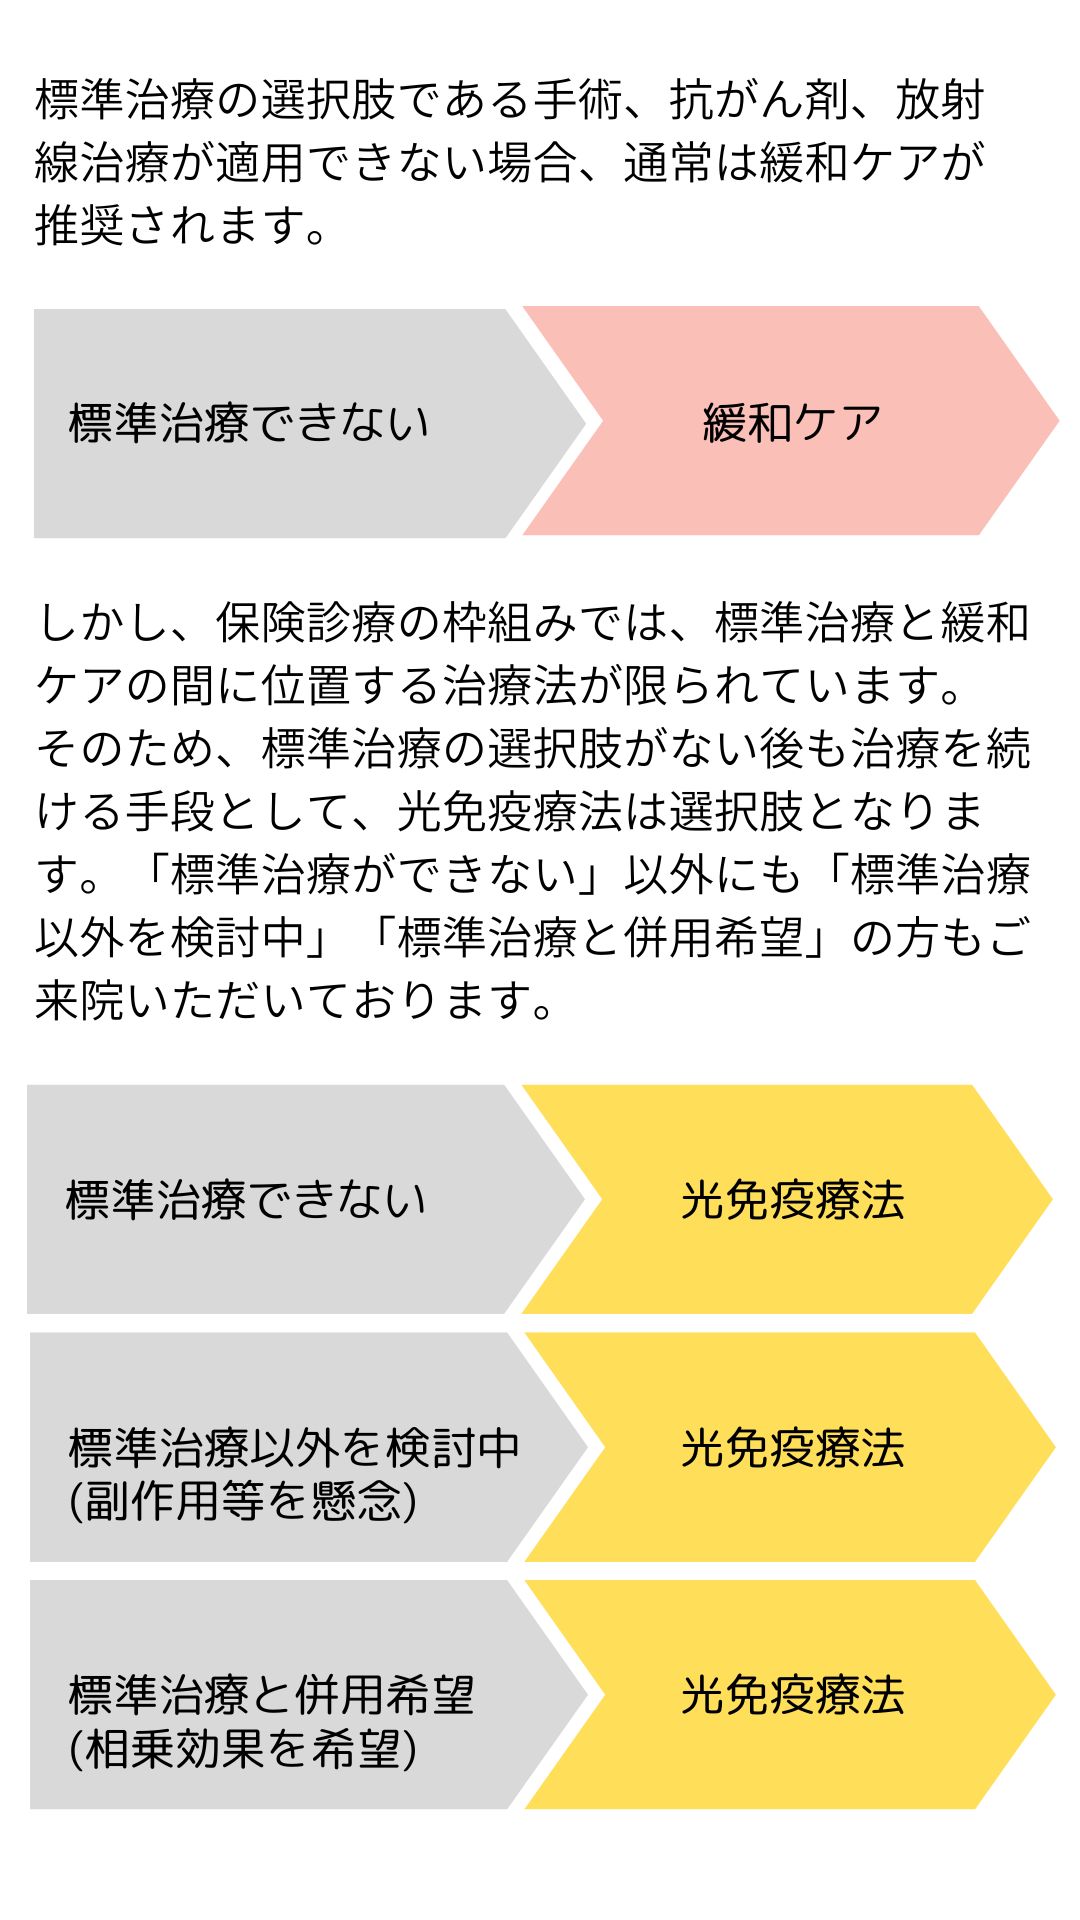

光免疫療法の主な位置づけ

Positioning of PDT